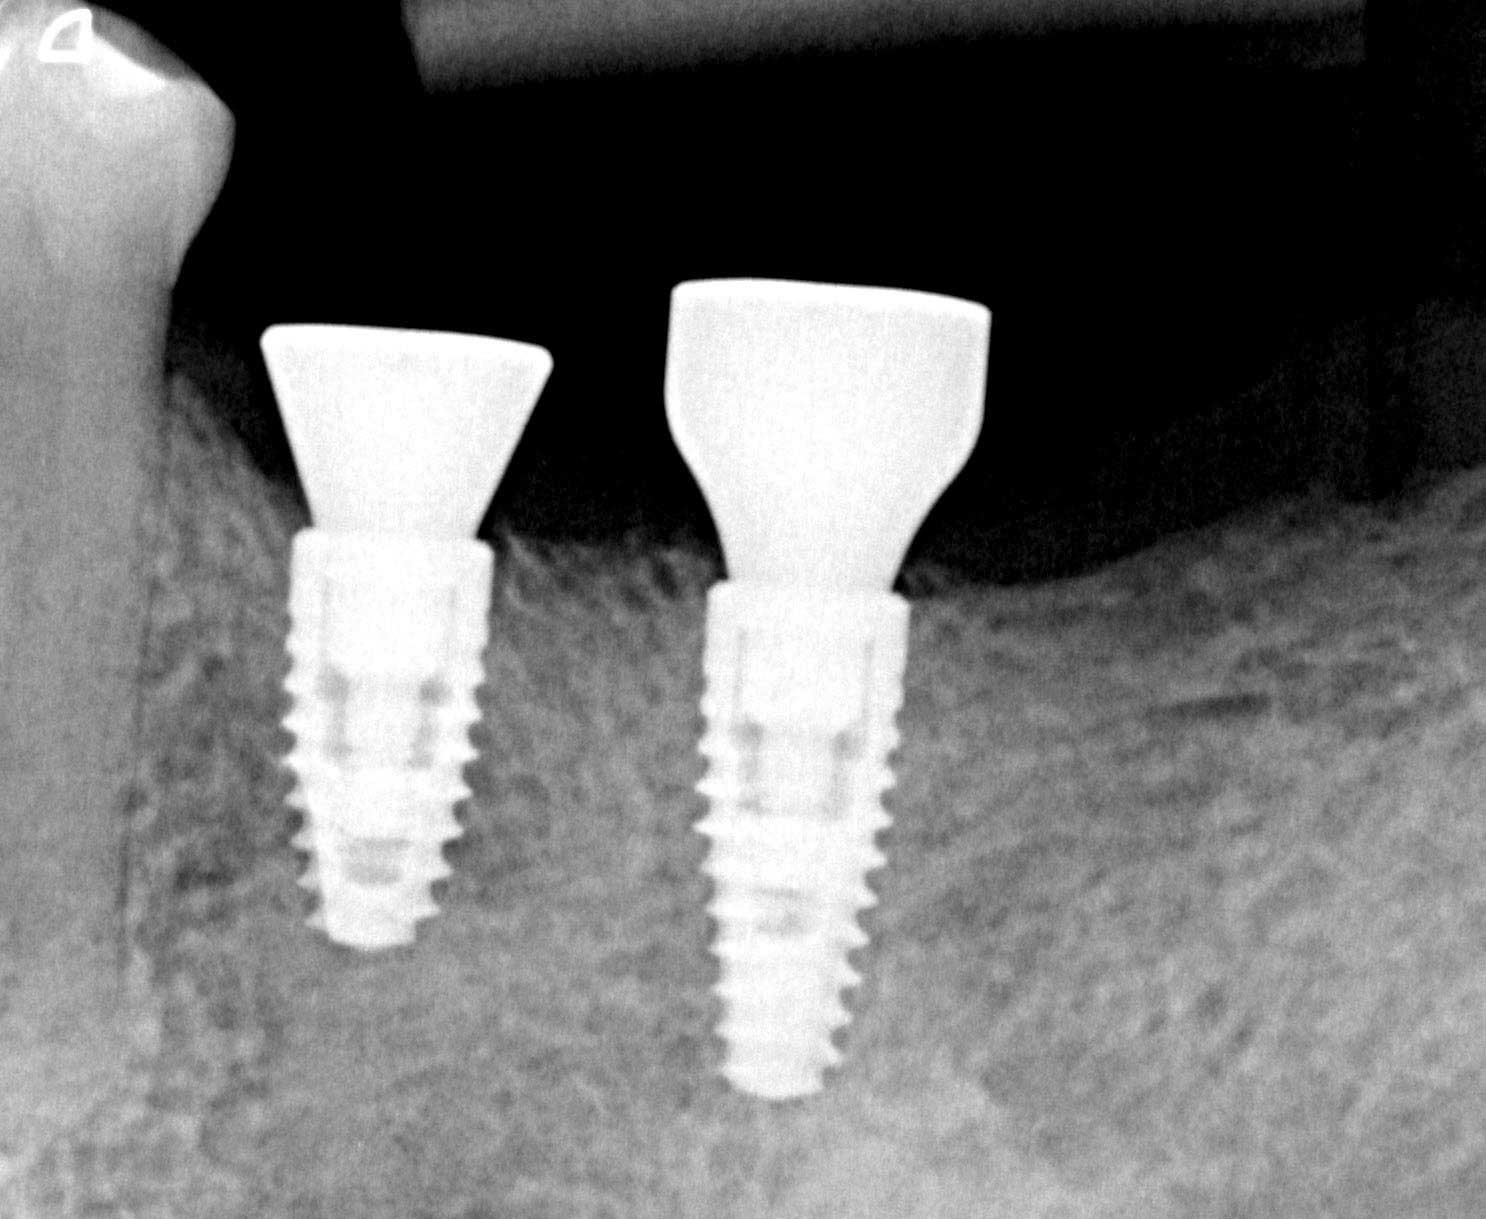

Three implants placed in a narrow posterior mandible